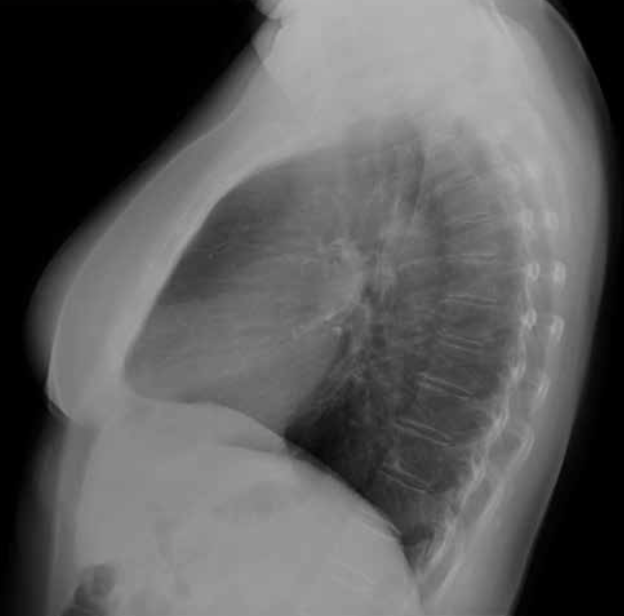

Hiperinsuflación. Patologías como el asma o el enfisema pueden cursar con un exceso de aire en los pulmones.

Sus hallazgos radiológicos son:

• Aplanamiento del hemidiafragma. Veremos el hemidiafragma derecho por debajo de la séptima costilla anterior.

• Horizontalización de costillas y aumento del espacio intercostal.

• Estrechamiento de la silueta cardiaca.

• Ensanchamiento del espacio aéreo retroesternal o retrocardiaco en proyección lateral.